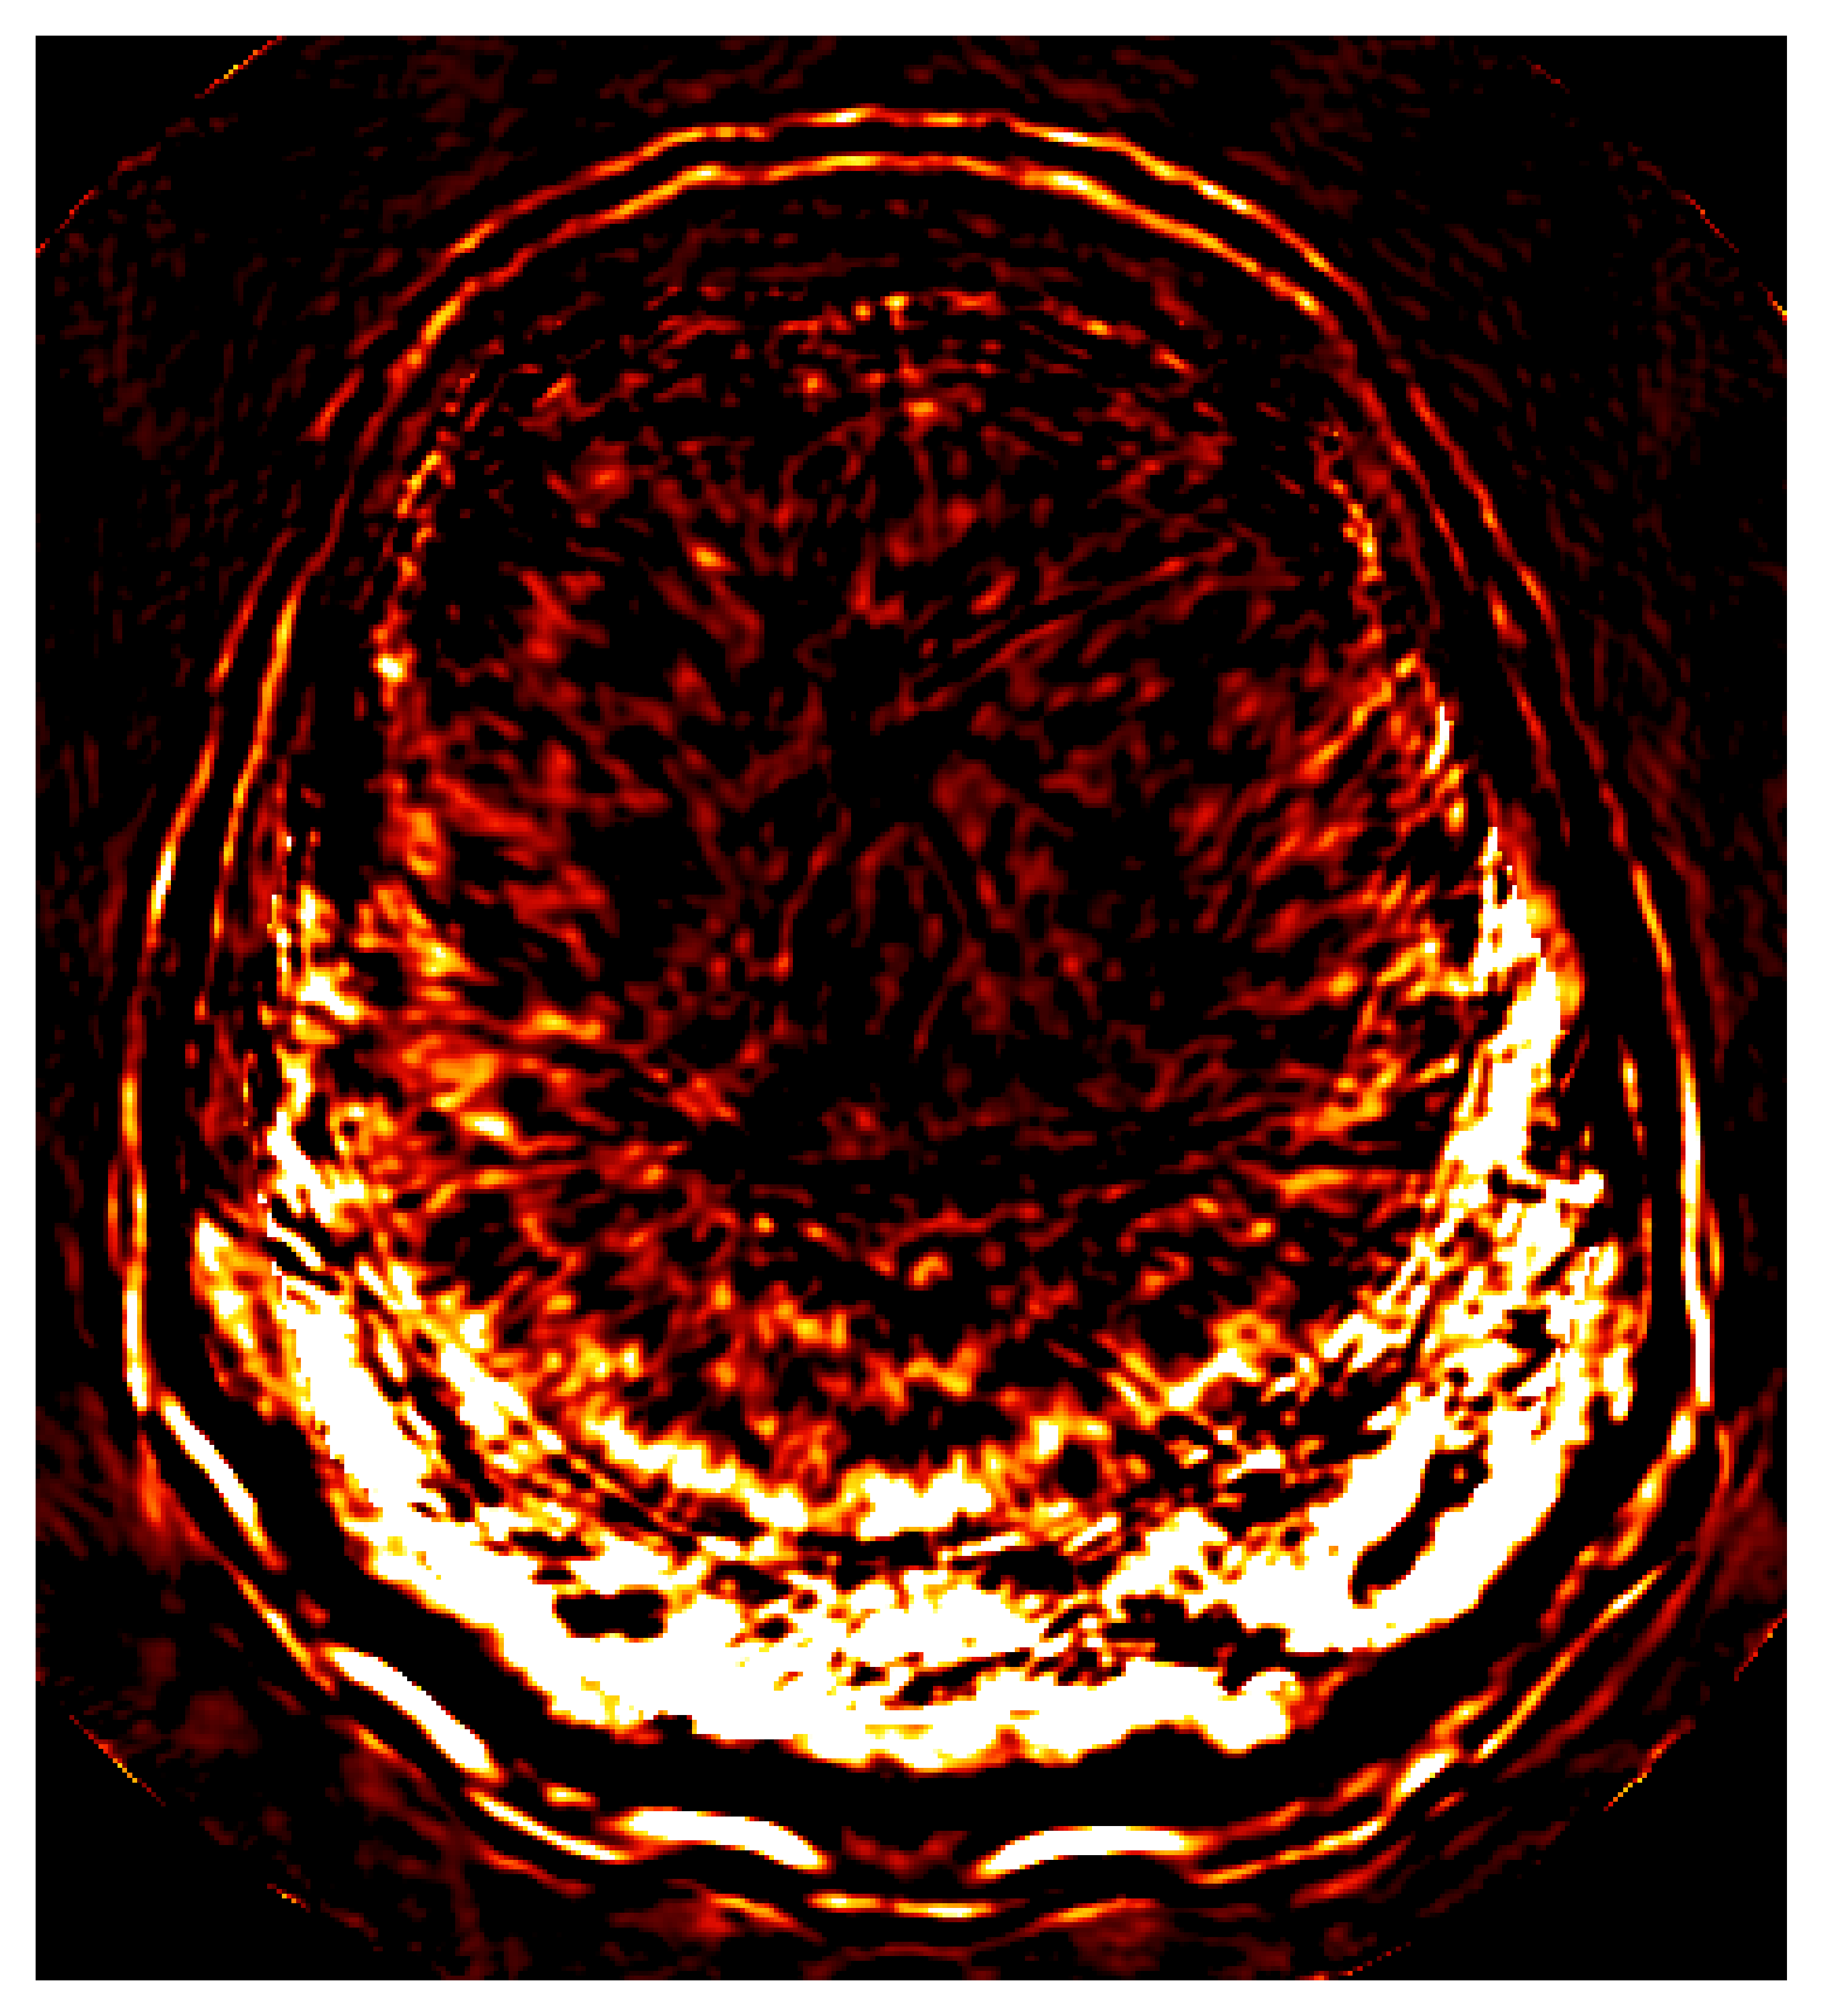

To overcome the end-to-end inference problem, we apply one iteration of ASPIRE by training a CNF on pairs, , where the ’s represent the score-based summary statistics at the fiducial points, , taken to be the uniform water velocity for all samples. An example of this initial summary statistic is shown in Figure 8. While the outer edge of the skull is reasonably well delineated, the inner edge of the skull is still poorly resolved and details inside the skull are mostly absent. However, the inference based on these initial summary statistics, shown in Figure 9, present a significant improvement over the baseline (cf. Figure 7), despite the presence of strong imaging artifacts in the summary statistics. The improvements concern the skull’s structure in particular, although details within the skull remain elusive due to the summary statistic’s limited information. To enhance fidelity further, ASPIRE 2 (shorthand for ASPIRE at iteration ) is applied by recalculating the score at the new posterior mean estimate for each training sample. Given these new training pairs, the next CNF is trained. While posterior sampling is efficient with CNFs (using Equation 4), recalculation of the score for each sample is computationally intensive, a topic we address in Section 6.6.